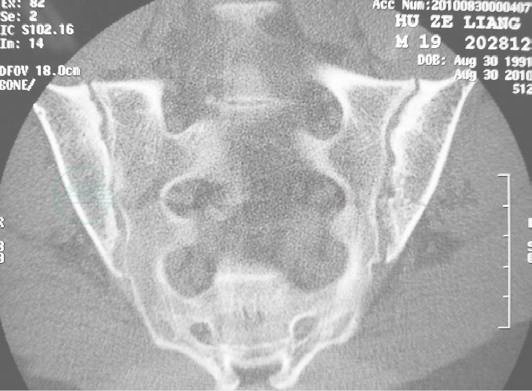

骶髂关节CT(图2):双侧骶髂关节硬化、不光滑,呈虫蚀样改变,以左侧为主。

图2

CT:双骶髂关节硬化,关节面不光滑,呈虫蚀样改变